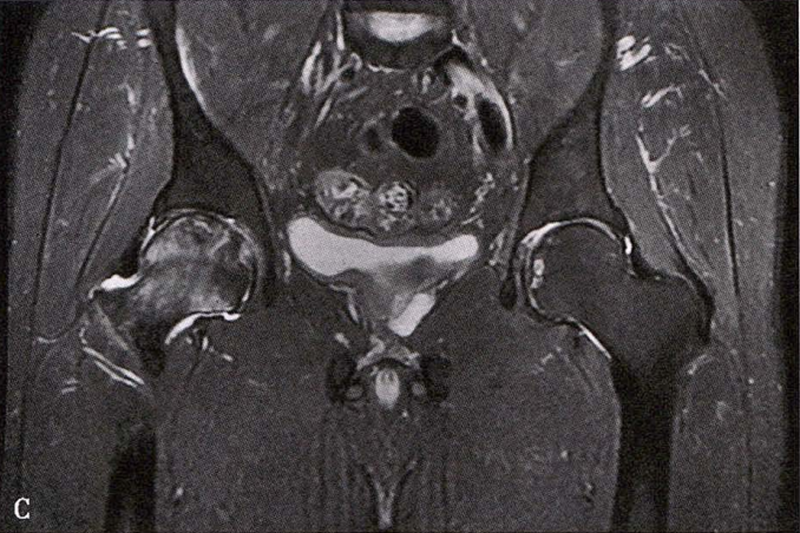

(2)MRI检查 MRI检查是早期诊断股骨头坏死最具特异性、灵敏度的检查方法。当怀疑有股骨头坏死,而X线片无明显异常时,应行MRI检查。诊断时可根据髋关节X线、MRI显示的坏死面积和塌陷程度进行ARCO分期。

冠状面及横断面MRI图像

MRI示双侧股骨头坏死,冠状面显示右侧股骨头坏死(图A、C),横断面显示双侧股骨头坏死(图B、D);T1加权像(图A、B)显示硬化带为低信号,T2加权像(图C、D)显示右侧骨坏死硬化带外围高信号的骨髓水肿,左侧无骨髓水肿。

A.男性,71岁,双侧股骨头坏死,右侧Ⅰ期、左侧Ⅲ期。X线片示双侧股骨头形态可,右股骨头未见明显密度改变,左股骨头关节面下见局限性骨密度减低及增高区(A1)。MRI(T2加权像)示右股骨头内双线征,左侧不规则形混杂信号,坏死区远端骨髓水肿(A2、A3)。